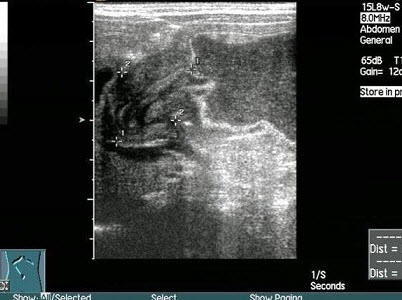

13、单项选择题

患者,右下腹压痛,体温38.5℃。根据右下腹声像图表现,诊断是()

A.腹膜炎

B.结肠癌

C.阑尾脓肿

D.单纯性阑尾炎

E.腹水

14、单项选择题 人体组织和体液中,哪一种最少引起声衰减()